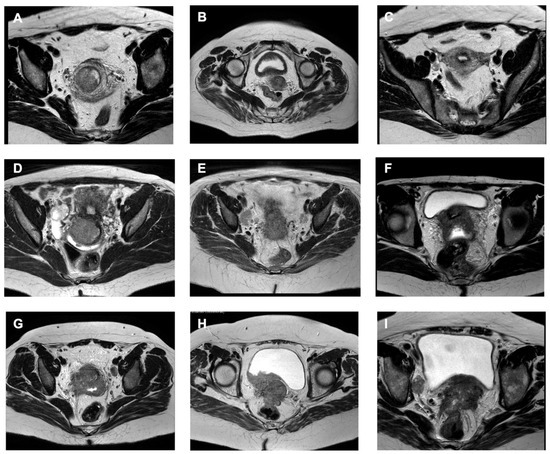

Image-Guided Adaptive Brachytherapy for Uterine Cancer: A Comprehensive Review

Background/Objectives: Image-guided adaptive brachytherapy (IGABT) has transformed the standard of care for locally advanced cervical cancer (LACC), enabling volumetric target definition and dose–volume histogram (DVH)-based planning to improve pelvic tumor control while limiting severe late toxicity. Methods: A comprehensive literature search [...] Read more.

Background/Objectives: Image-guided adaptive brachytherapy (IGABT) has transformed the standard of care for locally advanced cervical cancer (LACC), enabling volumetric target definition and dose–volume histogram (DVH)-based planning to improve pelvic tumor control while limiting severe late toxicity. Methods: A comprehensive literature search of PubMed/MEDLINE and Embase was done for articles published up to August 2024, using combinations of the following keywords and Medical Subject Heading (MeSH) terms: “cervical cancer”, “endometrial cancer”, “vaginal cancer”, “uterine neoplasms”, “brachytherapy”, “high-dose-rate”, “image-guided”, “MRI-guided”, “3D brachytherapy”, “IGABT”, “interstitial”, “locoregional control”, “toxicity”, “quality of life”, and “patient-reported outcomes”. Results: We summarized the contemporary evidence on IGABT for cervical, endometrial, and primary or recurrent vaginal cancers, focusing on local control, survival, late morbidity, and patient-reported outcomes. We described the key target volume concepts (gross tumor volume, high- and intermediate-risk clinical target volumes), and the role of MRI-, CT-, and ultrasound-based planning with intracavitary, intracavitary–interstitial, and interstitial applicators. Conclusions: Image-guided adaptive brachytherapy has redefined the standard of care for the management of locally advanced cervical cancer. Through the integration of volumetric target concepts, DVH-based dose reporting, and advanced imaging, IGABT has enabled consistent dose escalation to the residual tumor while accounting for organ-at-risk constraints, resulting in high local control rates and reduced severe morbidity compared with historical 2D brachytherapy. Full article